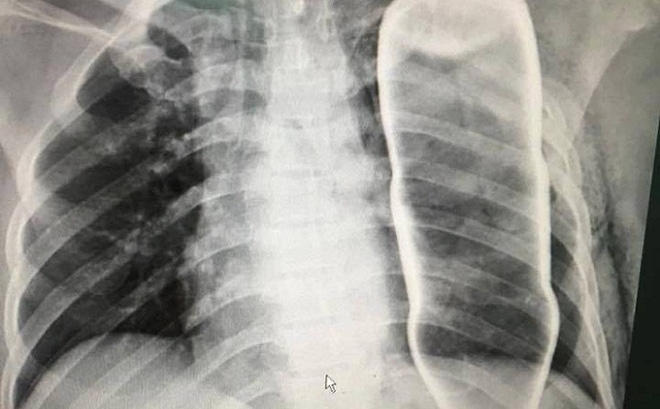

Hình ảnh chụp X - Quang vỏ chai thủy tinh trong lồng ngực bệnh nhân B.

Ngay sau đó, các bác sỹ đã tiến hành chụp X Quang, Citi và vô cùng kinh ngạc khi phát hiện một vỏ chai nước khoáng đang nằm gọn trong ngực của bệnh nhân B.